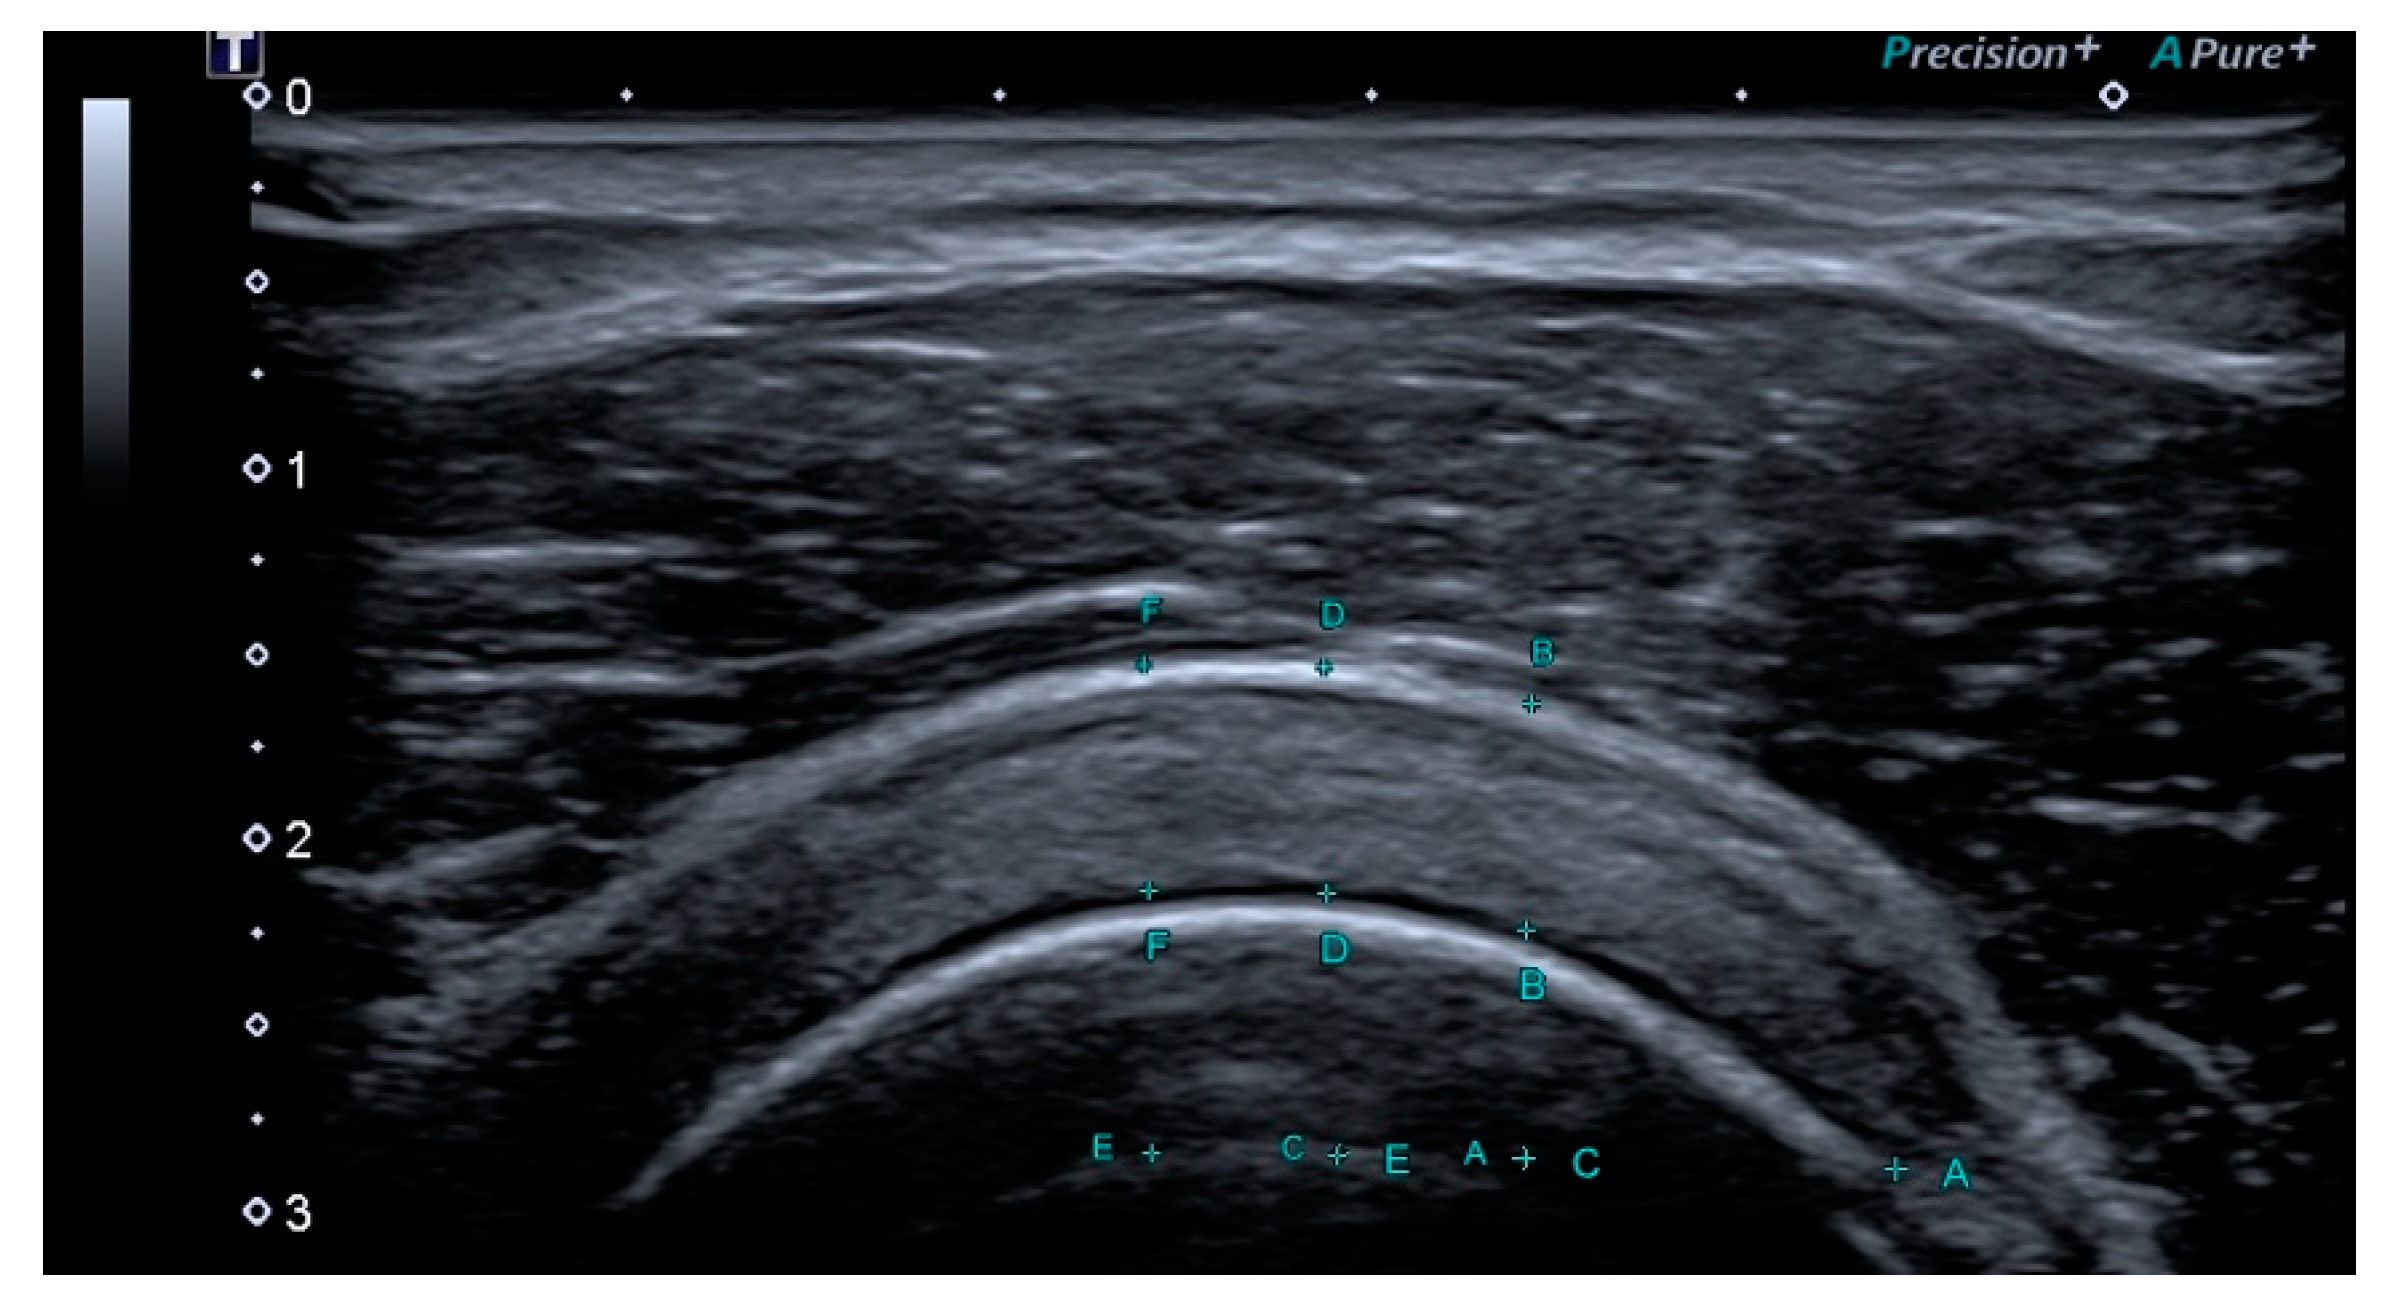

2.2.1. Outcomes Ultrasound Evaluation

2.2.2. Ultrasound Evaluation

| Thickness affected side T0 | 7.5 ± 0.9 |

| Thickness affected side T1 | 5.3 ± 1.3 |

| Thickness healthy side T0 | 4.5 ± 0.7 |

| Supraspinatus Thickness | 7.5 ± 0.9 | 6.2 ± 0.9 | −0.9 to −1.6 | 4.5 ± 0.7 | <0.05 |